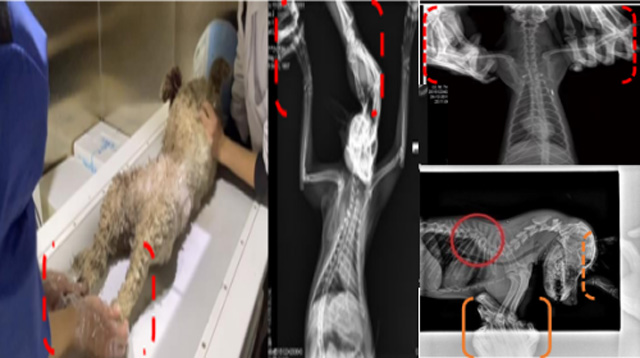

現在寵物醫療設備得到高速發展,現在有越來越多的寵物診療機構配置X射線裝置如寵物DR。寵物骨折或者有其他疾病不能通過直觀看出來的。寵物診所醫生都會使用寵物DR來做輔助檢查。但是有時候寵物醫生沒有加強防護,就在寵物DR室給寵物拍X片做檢查。這樣也是會受到X射線的輻射。因為X射線上崗是屬於職業病危害崗位。長期的輻射會對人體造成一定的危害。寵物醫生也需要接受X射線照射的上崗前都必須進行放射工作人員的職業健康體檢。體檢不合格的話是不能擔任放射工作的。未經上崗前職業健康體檢的勞動者從事接觸職業病危害作業的行為,已經違反了《中華人民共和國職業病防治法》第三十五條規定,依據《中華人民共和國職業病防治法》第七十五條規定,需要進行整改罰款。開展寵物放射診療活動,在日常工作中,對本機構的X射線危害的職業病防治,需要知道並做到以下內容:

建造X射線機房時尋找專業防護施工隊伍,對機房四方及上下方牆體進行屏蔽防護,盡可能隔室操作,使用鉛防護門並安裝工作指示燈張貼警示標識進行提醒。放射工作人員跟寵物主進入DR室需要穿戴鉛衣、鉛帽、鉛手套等做好防護,減少X射線的輻射。避免暴露在照射範圍中。寵物醫生上崗前、在崗時、離開崗位時候的職業健康體檢。如果檢查異常就需要複查跟調離放射崗位。實施個人劑量監測和防護知識培訓。並在勞動合同中向放射工作人員告知X射線危害相關內容。定期委托職業技術服務機構對機房防護、放射診療設備性能進行檢測。不能忽略了對人的保護。